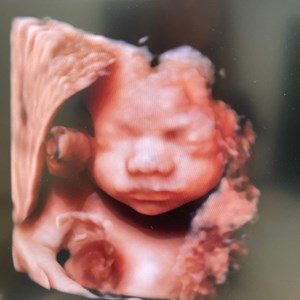

Billeder fra livets begyndelse ✨ Scanning i 9. graviditetsuge. Billede i 2D og 3D. Læg mæ...

hjertelyd_scanningsklinik Se lige ham den lille charmetrold her 😍 Tilbagelænet stil med ...